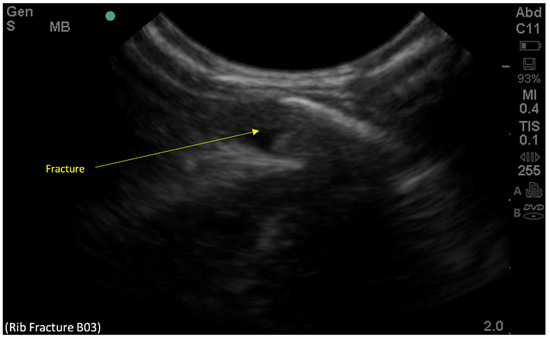

2. Case Presentation